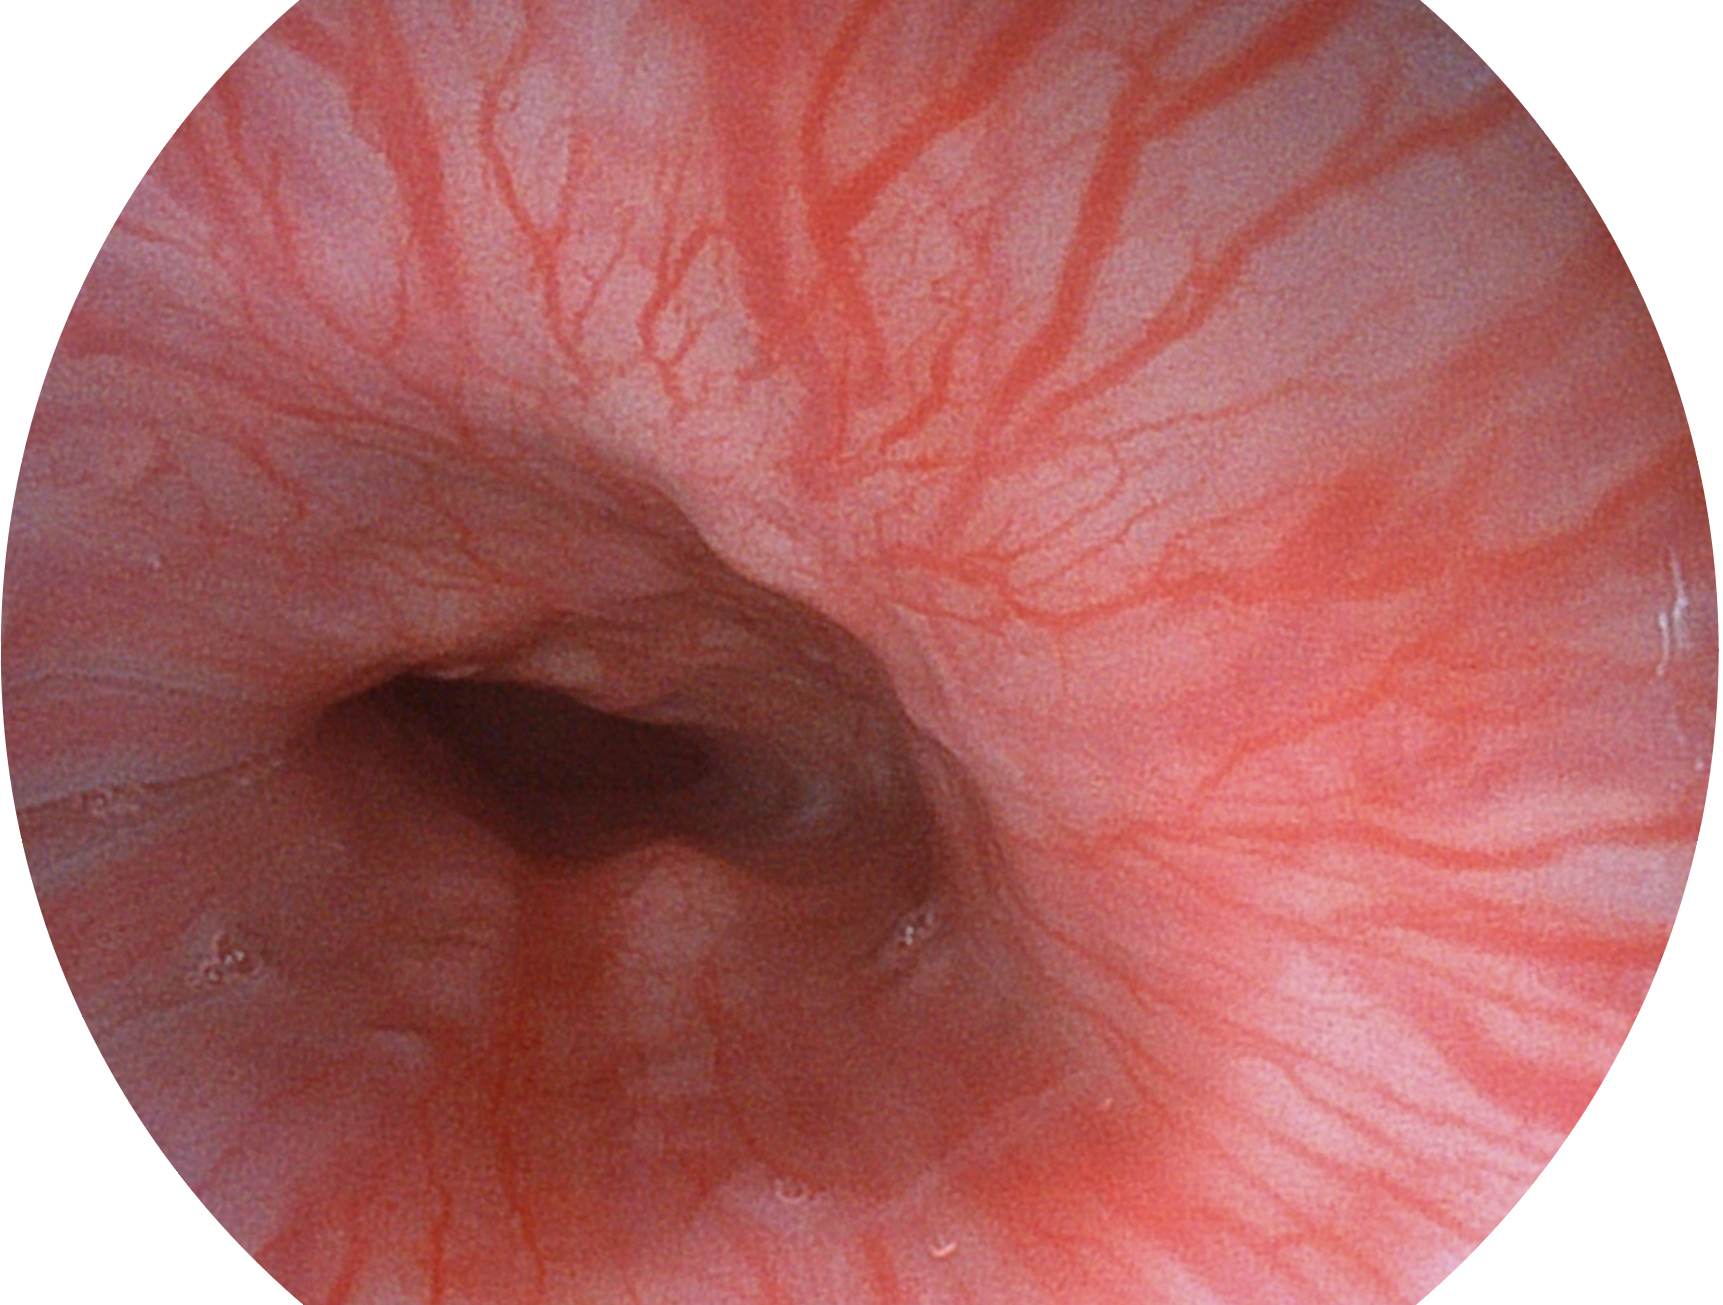

美狮贵宾会官网新开发的内镜染色技术,主要是基于多波长LED 光源的开发,VLS-55Q 四波长LED 光源是由四个不同颜色的LED光按照相应照明模式所规定的特定发光比例进行合束后形成,合束后形成的照明光的光谱由红光、绿光、蓝光及蓝紫光这四个不同的波段范围构成。具有更高光谱自由度,通过光谱比例的控制,实现了聚谱成像技术,英文全称为“Spectral Focused Imaging, SFI”,缩写为“SFI”和光电复合染色成像技术,英文全称为“Versatile Intelligent Staining Technology, VIST”,缩写为“VIST”。